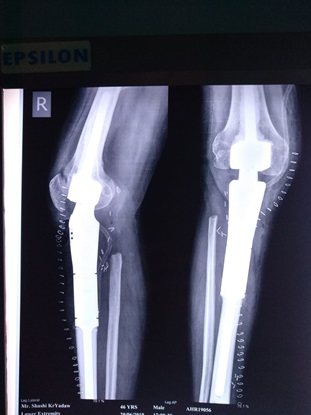

Children and adults with tumors and tumor-like disorders of the bone and soft tissue, such as bone metastases, sarcomas, benign and malignant tumors of the bone or soft tissue, and pathologic fractures, are treated by the Division of Orthopaedic Oncology, which provides them with the highest quality care.

Orthopedic oncology, also known as Musculoskeletal Oncology, focuses on the diagnosis and treatment of both benign and malignant bone tumors, along with other unusual lesions affecting the musculoskeletal system. Bone cancer and soft tissue sarcomas, though rare, demand a comprehensive, multidisciplinary approach to diagnosis and treatment.